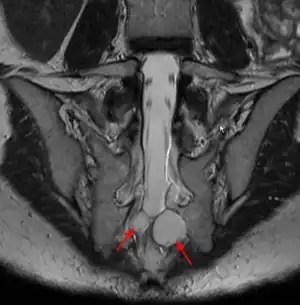

| MRI image showing a Tarlov cyst | |

Location

Tarlov cysts are most commonly located in the S1 to S4/S5 region of the spinal canal, but can be found along any region of the spine. They usually form on the extradural components of sacrococcygeal nerve roots at the junction of dorsal root ganglion and posterior nerve roots and arise between the endoneurium and perineurium.[10] Occasionally, these cysts are observed in the lumbar and thoracic spine.[7] However, these cysts most commonly arise at the S2 or S3 junction of the dorsal nerve root ganglion.[11][12] The cysts are often multiple, extending around the circumference of the nerve, and can enlarge over time to compress neighboring nerve roots, to cause bone erosion.[13] The cysts may be found anterior to the sacral area and have been known to extend into the abdominal cavity. These cysts, though rare, can be found to grow large - over 3–4 centimetres (1.2–1.6 in) in size, often causing severe abdominal pain from compression on the cyst itself as well as adjoining nerves.

MRI

MRI, or Magnetic Resonance Imaging, is considered the imaging study of choice in identifying Tarlov cysts. MRI provides better resolution of tissue density, absence of bone interference, multiplanar capabilities, and is noninvasive. Plain films may show bony erosion of the spinal canal or of the sacral foramina. On MRI pictures, the signal is the same as the CSF one.